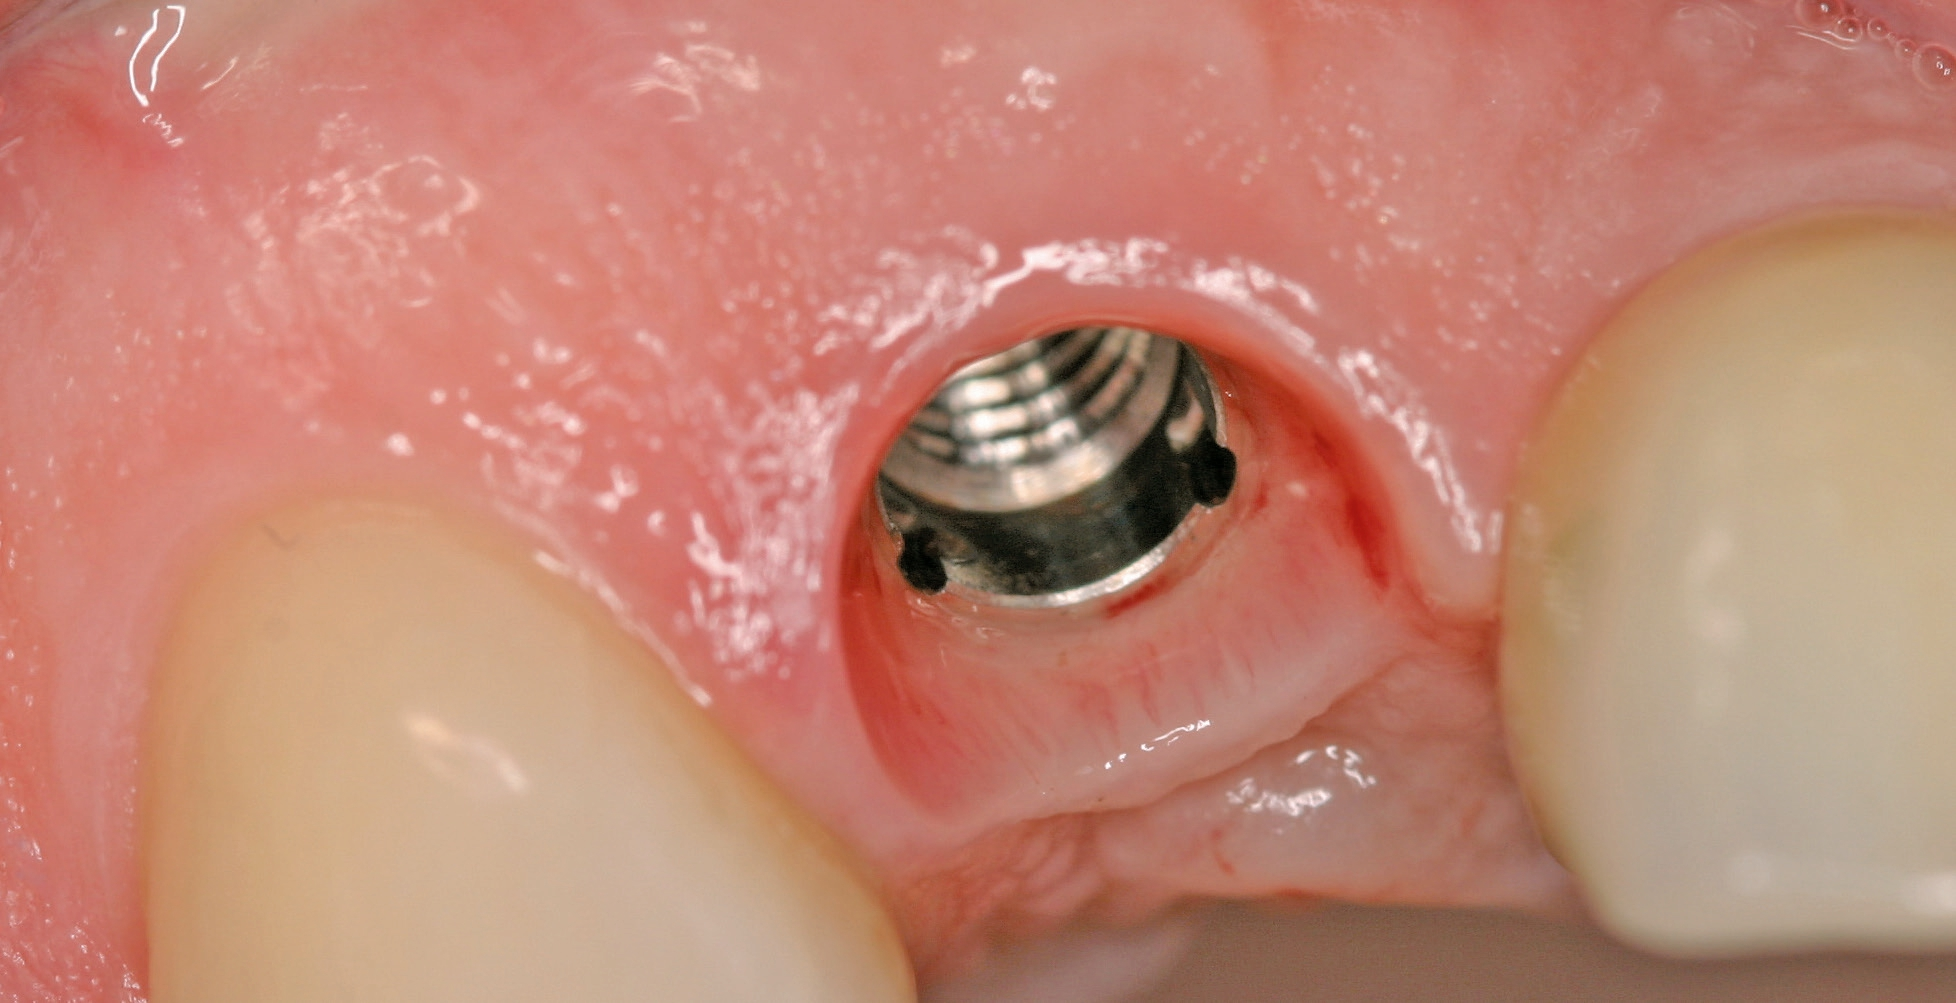

Implantation: 7 Monate nach Augmentation

Trotz der schlechten, hart- und weichgewebigen Grundvoraussetzungen konnte der Kieferkamm zufriedenstellend rekonstruiert werden. Die Augmentation des kombinierten, horizontalen und vertikalen Defekts mit Yxoss CBR®, Geistlich Bio-Oss®, Geistlich Bio-Gide®, autologem Knochen und PRF ermöglichte die Implantation mit hoher Primärstabilität in den rekonstruierten Bereich.